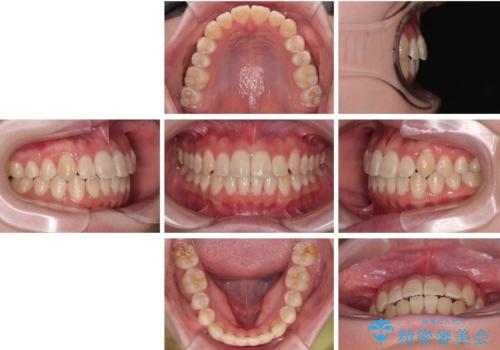

【モニター】前歯のデコボコをスッキリ解消!目立ちにくいワイヤー矯正でスピーディに治療完了

- 「前歯のデコボコ(叢生)をきれいに整えたい」とのことでご来院されました。

マウスピース矯正も検討されていましたが、「装着時間の自己管理が難しそう」「なるべく早く治療を終えたい」とのご希望から、ワイヤー矯正を選択されました。

目立ちにくさと費用のバランスを考慮し、プラスチックブラケット+メタルワイヤーを採用。日常生活でも装置の存在感を気にせずお過ごしいただけます。

患者様の協力もあり、およそ1年間で治療を完了。スムーズな歯の移動を実現しました。

上下の正中(真ん中のライン)もずれることなく、バランスの取れた美しい歯並びに。笑顔に自信を持てる仕上がりとなりました。